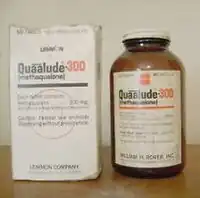

Quinazolinone

Quinazolinones are a class of depressants that are rarely used anymore. Quinazolinones have powerful sedative, hypnotic, and anxiolytic effects. Quinazolinone's structure is very similar to that of some antibiotics. Quinazolinone's main mechanism of action is binding to the GABAA receptor.[162] It does not bind to the ethanol, barbiturate, neurosteroid, or benzodiazepine site.[162] Instead, it binds on a site directly between the GABRB2 (β2) and (α1) GABRA1 proteins on the GABAA receptor.[162] The anesthetic etomidate and anticonvulsant loreclezole may also bind to this site.[162]

Methaqualone hydrochloride and quinazolinone anxiolytics and hypnotics are referred to as "quaaludes", "ludes", and "disco biscuits". Methaqualone was very commonly abused in the western world during the 1960s and 1970s. Methaqualone was mainly prescribed for insomnia, as it was thought to be safer than barbiturates and carbamates.[165] Methaqualone became highly abused by many, including celebrities, after its introduction in 1965.[163] Methaqualone was first synthesized in India in 1951 by Indra Kishore Kacker and Syed Husain Zaheer, who were conducting research on finding new antimalarial medications.[166][167] The drug name "Quaalude" (methaqualone) is a portmanteau, combining the words "quiet interlude". Methaqualone was discontinued in the United States in 1985, mainly due to its psychological addictiveness, widespread abuse, and illegal recreational use. Nonbenzodiazepines and benzodiazepines are now used to treat insomnia instead. Methaqualone is now a Schedule I substance. Some quinazolinone analogues are still sold online. They come with the risk of seizures.

Large doses of methaqualone can cause euphoria, disinhibition, increased sexuality and sociability, muscle relaxation, anxiolysis, and sedation. Today, methaqualone is widely abused in South Africa. Many celebrities have used quinazolinone, most notably methaqualone. Bill Cosby admitted to casual sex involving the recreational use of methaqualone.[168][169][170] 18-year-old actor Anissa Jones died from an overdose of cocaine, PCP, methaqualone, and the barbiturate Seconal. Billy Murcia, a drummer for the rock band New York Dolls, died at 21 when he drowned in a bathtub while overdosing on heroin and methaqualone.[171]

- Methaqualone (Quaalude, Sopor, Mandrax)